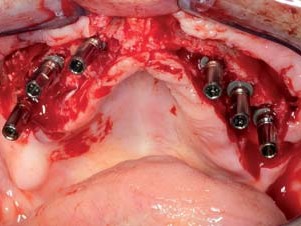

Im August 2012 wurden bis auf Zahn 38 alle Zähne extrahiert. Nach einer Ausheilzeit von zwei Monaten erfolgte der implantatchirurgische Eingriff. Für den Oberkiefer waren sechs und für den Unterkiefer vier Implantate geplant. Weng et al.⁷ haben in einer Studie gezeigt, dass eine Teleskopprothese auf nur zwei Pfeilern im Eckzahnbereich des Oberkiefers, ob zahn- oder implantatverankert, keine gute Prognose hat. Die exakte Position und Ausrichtung der Implantate wurde mittels laborgefertigter Positionierungsschablonen, die anhand der Wachsaufstellungen angefertigt worden waren, festgelegt und kontrolliert. Die Ankylos A und B Implantate (Dentsply Implants, Mannheim) mit 3,5 und 4,5 mm Durchmesser sowie 9,5 und 11 mm Länge wurden in Regio 12, 14, 16, 22, 24, 26 sowie 32, 34, 42 und 44 eingebracht. Dabei musste im Oberkiefer der Alveolarkamm geglättet und im anterioren Bereich horizontal erweitert werden. Dies geschah mittels Bone Splitting. Ferner wurde bei Regio 16 ein externer Sinuslift vorgenommen. Amalgamablagerungen der alten WSR in der Unterkieferfront wurden während des Eingriffs entfernt. Die Implantate heilten gedeckt ein (Abb. 3–10).